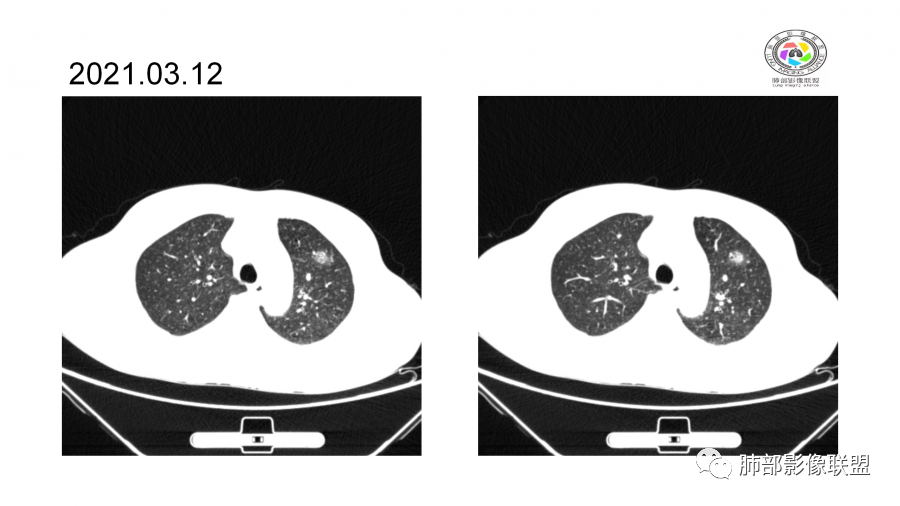

一月后:

南边:

病灶此起彼伏

中年男性,高血压,肾功能衰竭,贫血病史,尿潜血阳性。3.8双肺野多发斑片磨玻璃实变影,结节影,边缘模糊,周围有晕征,内见支气管充气征,主要沿支气管血管束分布,部分胸膜下分布,3.12号病灶有吸收好转,4.8号斑片实变影基本吸收,主要沿支气管血管束分布结节影,边缘平直收缩,4.28病灶大部分吸收好转,双肺支气管血管束增粗,有少量结节影。考虑ANCA相关性血管炎可能性大,第一次片子觉得隐球菌不排除,但是后面没有抗真菌治疗就吸收了,觉得隐球菌可能性不大。

胸部CT:双肺多发实性斑片影,散在GGO。实性斑片周围可见晕征、边缘模糊不清,病灶于肺外围区域优势分布。肺门区血管影增粗,支气管套袖,目测肺动脉增粗。3月、4月复查肺内实性斑片病灶呈游走性,此起彼伏。